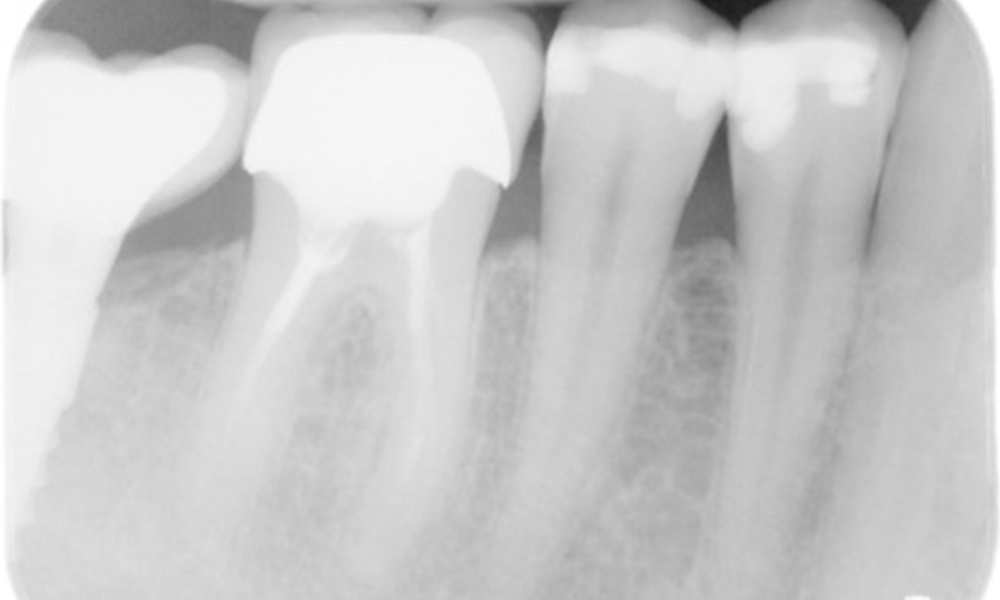

The X-ray images show the bone loss.

X-ray images (or bitewing X-rays)

X-ray images (or bitewing X-rays) taken on: 18/02/2021